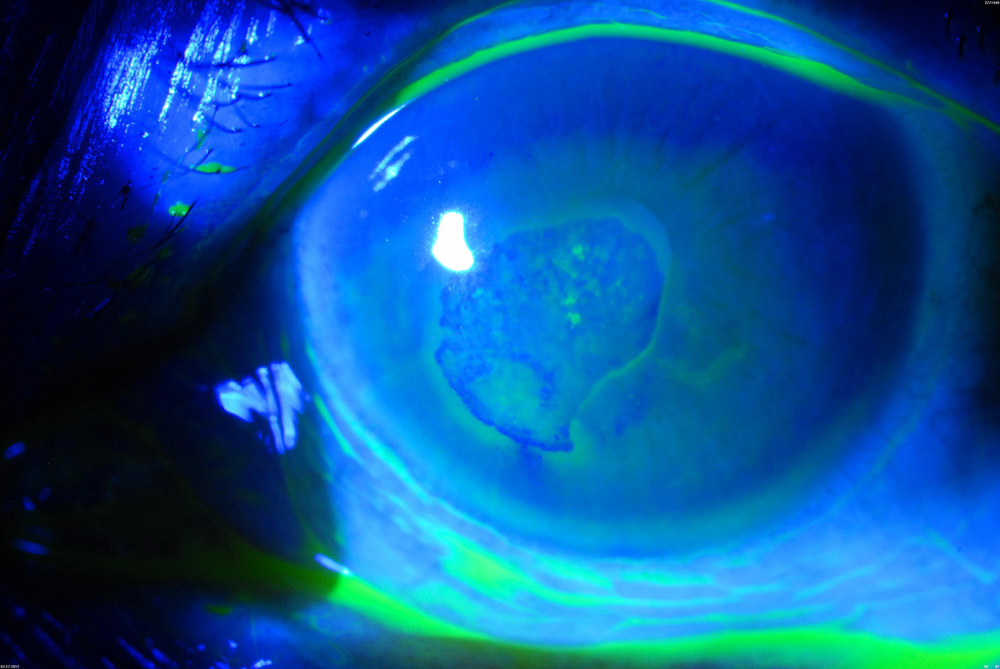

Dr. Rapuano took the stance that epithelial debridement with diamond burr polishing of Bowman’s layer is the better choice. One problem with recurrent erosions, he said, is there is a large spectrum of slit lamp findings, often delaying the actual diagnosis. Medical treatment for recurrent erosions includes tears/ointments, as well as bandage contact lenses and steroids.

Dr. Yoo spoke about the use of PTK. PTK can be indicated in a number of scenarios, including recurrent erosions. She added that it’s important preoperatively to illicit a history of any conditions that could adversely affect wound healing. It’s also important to know any previous history of HSV keratitis, as this is a relative contraindication to using the excimer laser. On exam, physicians should pay attention to the type and depth of pathology at the slip lamp and surrounding corneal thinning. Looking at corneal pachymetry and performing the corneal sweep test to identify loose epithelium are also important, she said.